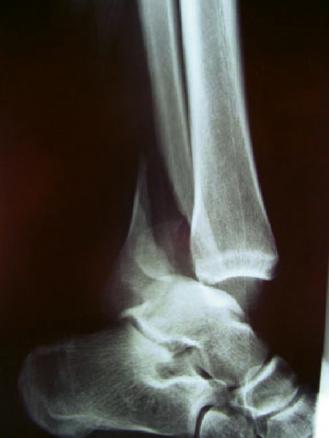

Luxation tibio-talienne associée

2. Luxation tibio-talienne associée